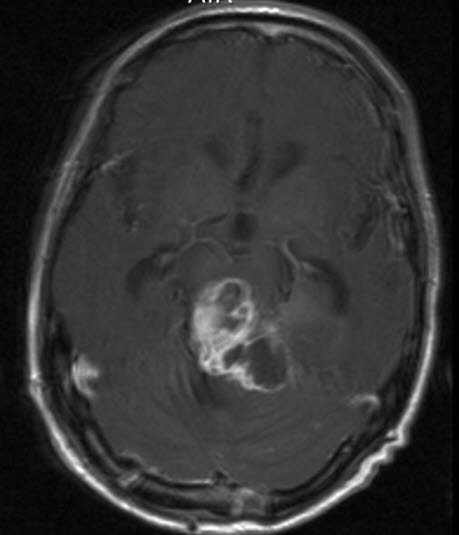

Pineoblastom, aksialt snitt

Gjengitt med tillatelse av Radiologisk avdeling, Universitetssykehuset Nord-Norge